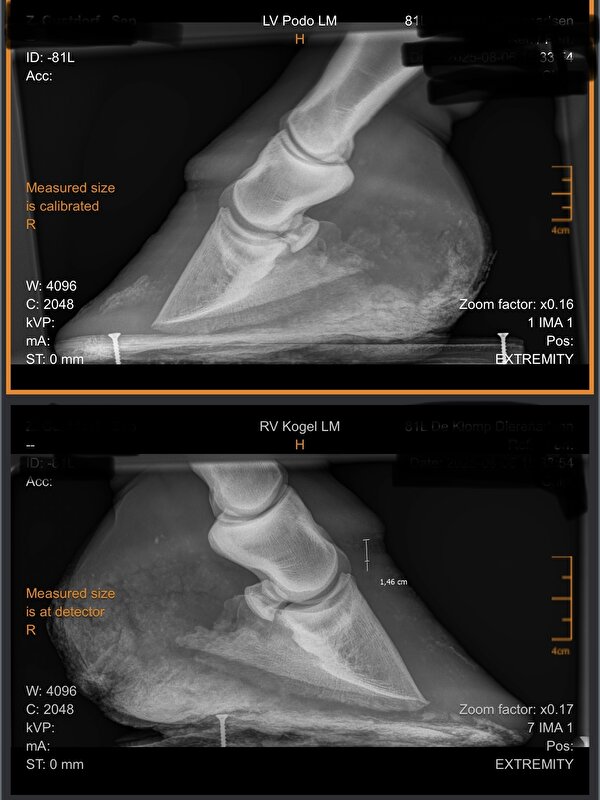

Maar vaak is het bij bevangenheid zo dat er meerdere (kleine) oorzaken de trigger veroorzaken. Persoonlijk zou ik die eerst willen uitsluiten voordat ik het op de cushing gooi en de pony laat inslapen. Al is het maar dat je zelf vrede hebt met de beslissing.

Elisa2 schreef:Hm dat is helaas niet mijn ervaring met HB bij PPID. Hebben twee paarden gehad met exact hetzelfde beeld, HB door de Cushing en geen andere oorzaken en bij beide was het, het begin van het einde helaas en een rot lijdensweg.